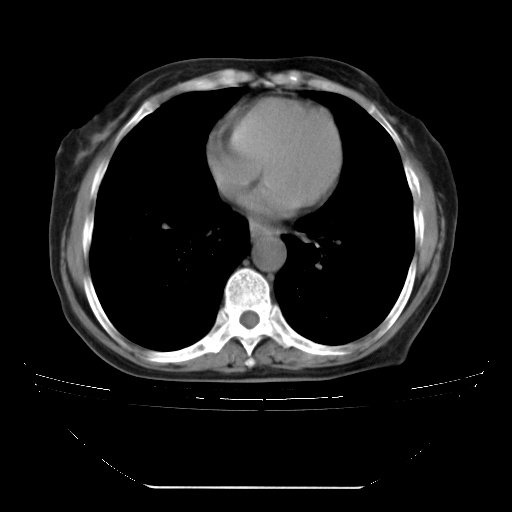

患者女性,72岁,慢性咳嗽3月余,曾抗炎治疗无效果,最近抗结核治疗约半月余,症状缓解。

ct示两肺粟粒状病灶,以两肺上叶尖后段及下叶背段分布为主;首先考虑结核。请战友们分析。

查原发灶吧,肺内转移瘤!肝内也有病灶,需强化明确。

两肺内病灶呈小结节状和树芽状,纵膈的肿大的淋巴结密度不均匀,并见有钙化,考虑为两肺结核可能更大些。

两肺内病灶呈小结节状和树芽状,纵膈的肿大的淋巴结密度不均匀,并见有钙化,多形态病灶,考虑为两肺结核,肝内考虑小囊肿。